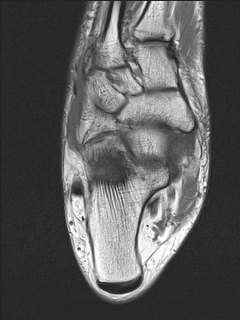

Coronal Ankle 1

Calcaneus

Cuboid

Intermediate Cuneiform

Lateral Cuneiform

Medial Cuneiform

Metatarsal [I]

Metatarsal [II]

Navicular

Peroneus Longus

Talus